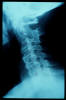

Artrosis cervical.

Artrosis cervical

APR Cervicoartrosis